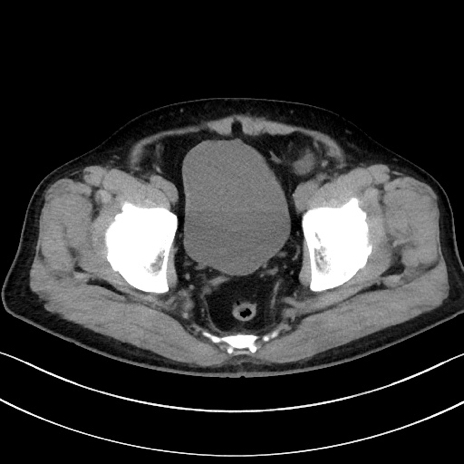

症例15(横断像)

【症例】70歳代男性

【主訴】腹痛

【現病歴】今朝から腹痛あり。全体的に痛い。特に左上の方。排ガスが今日はない。冷や汗が出る。

【既往歴】直腸癌術後

【身体所見】左側腹部〜上腹部に圧痛あり。腹膜刺激症状明らかなではない。軽度反跳痛。左下腹部に術後瘢痕あり。

【データ】WBC 7700、CRP 0.02